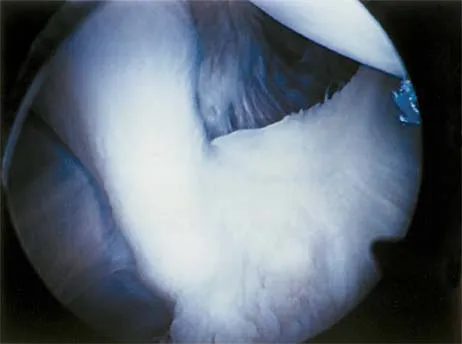

Question 6:

Figure 19 shows an arthroscopic view from the anterior lateral portal of the knee looking into the suprapatella pouch. The use of an electrothermal device during this procedure most commonly causes significant postoperative complications by damaging which of the following structures?

Correct Answer: Superior lateral geniculate artery

Explanation:

While it is possible to damage any of these structures, unrecognized intraoperative laceration without adequate coagulation of the superior lateral geniculate artery is common. This can result in significant postoperative hemarthrosis and a return to surgery when bleeding cannot be controlled. Cash JD, Hughston JC: Treatment of acute patella dislocation. Am J Sports Med 1988;16:244-249.